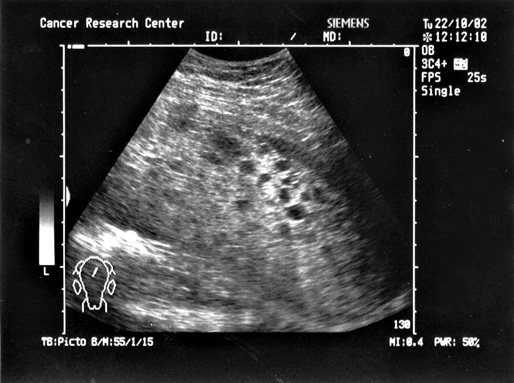

Рисунок 5. Ультразвуковая томограмма больной с пузырным заносом

Рисунок 6. Ультразвуковая томограмма больной с хориокарциномой матки

Однако в последнее время диагностическая роль этих исследований сведена к минимуму. Это обстоятельство связано с появлением УЗТ, которая в значительной мере превосходит информативность и чувствительность других методов, что обусловило ее приоритетное значение и широкое повсеместное использование при этом заболевании. УЗТ не только дает возможность с высокой степенью достоверности определить наличие опухоли и ее локализацию в матке, но, благодаря неинвазивности метода, позволяет применять его неоднократно в динамике заболевания, как контроль за эффективностью химиотерапии, а также как один из критериев излеченности.